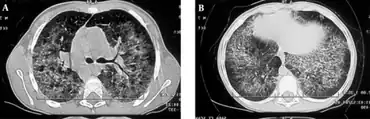

The diagnosis of hyper IgM syndrome can be done via the following methods and tests:[1]

- MRI

- Chest radiography

- Pulmonary function test